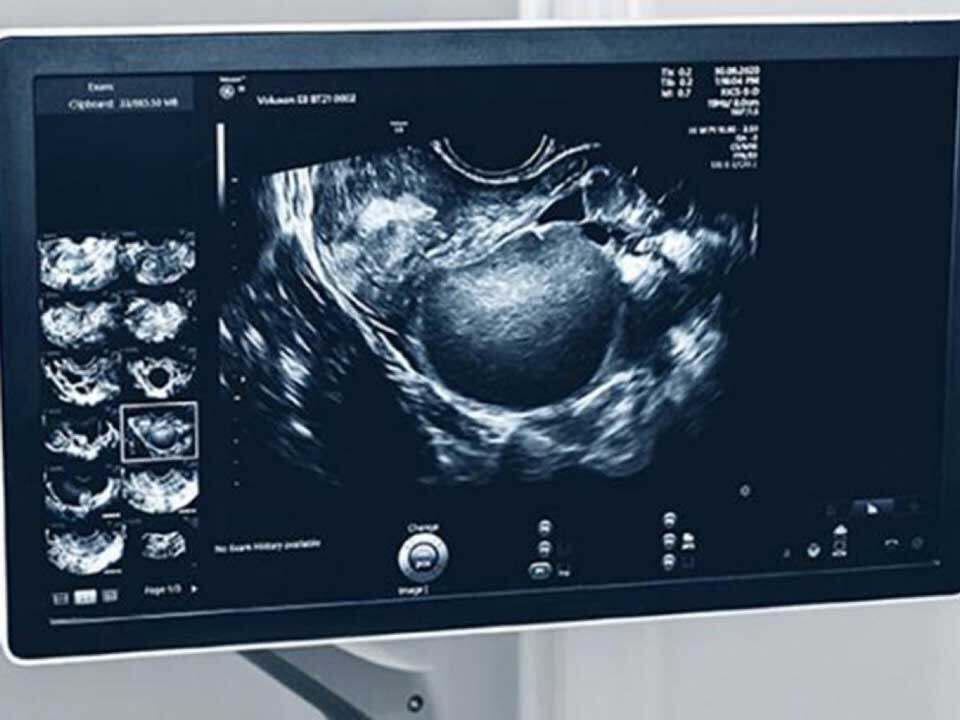

The IMAGENDO Program involves the use of less invasive specialist scans such as transvaginal ultrasounds, gynaecological MRIs and artificial intelligence to diagnose endometriosis.

“The technology is currently 90 per cent accurate in distinguishing positive from negative cases which is similar to that of a specialist endometriosis doctor,” Dr Avery said.